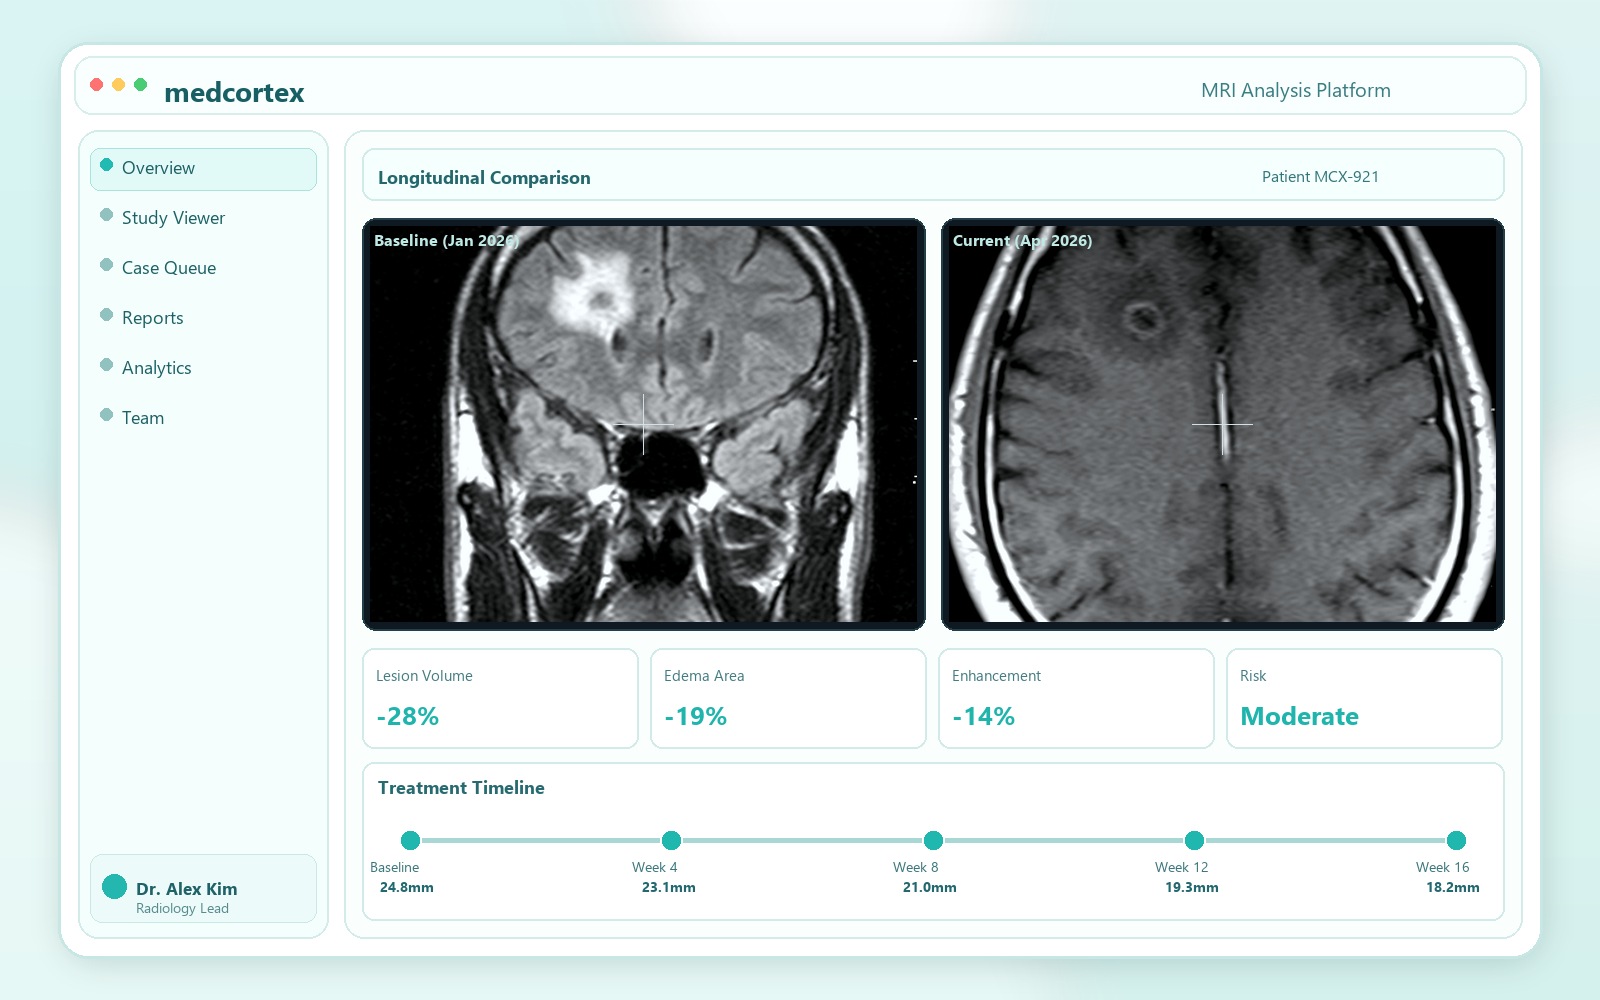

Our in-house trained neural network highlights suspicious regions, quantifies change over time, and helps specialists prioritize urgent studies without disrupting existing workflows.